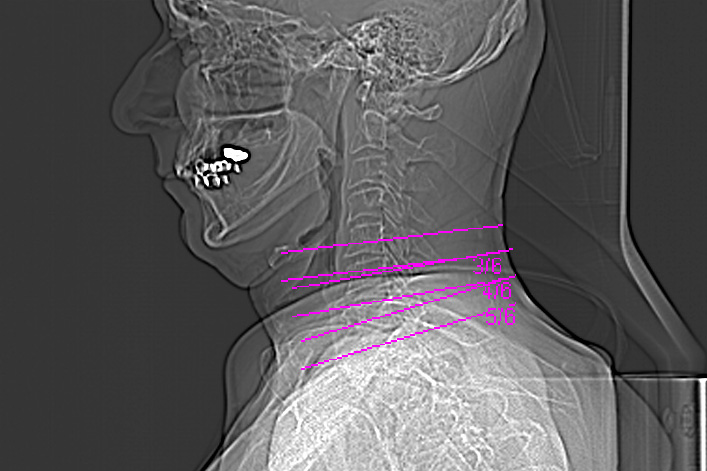

Für das Bild der Woche wurde dieses Mal eine besondere Vorrichtung benutzt. Auf Grund ständiger Schmerzen im rechten Oberarm suchte ich meinen Hausarzt auf. Nach einer kurzen Untersuchung vermutet er etwas im Halswirbelbereich und schickte mich zum Radiologen. Dort wurde eine Computer Tomografie (CT) gemacht. Die Bilder erhielt ich auf einer CD für meinen Hausarzt.